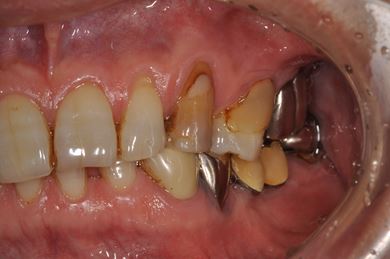

インプラントの症例写真 IMPLANT

骨再生インプラント治療+セラミック治療

| 性別/年齢 | 男性 / 60歳 | ||||||||||||||||||||||||||||||||

| 主訴 | 右上奥歯が動いて痛みがある。 | ||||||||||||||||||||||||||||||||

| 治療方針 | サイナスリフトにて上顎洞を拳上し、骨再生療法を用いてインプラント治療を可能にする。 | ||||||||||||||||||||||||||||||||

| 治療内容 | インプラント5本(サイナスリフト、GBR)、ハイブリッドセラミッククラウン5本、メタルボンドセラミッククラウン1本(メタルボンド用土台1本)、ハイブリッドセラミックインレー、遊離歯肉移植手術 | ||||||||||||||||||||||||||||||||